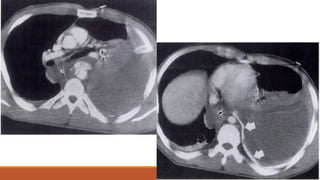

Diaphragmatic tear bowel herniation. CT scan shows intrathoracic herniation of bowel and

fat. Note the torn end of the midiaphragm (arrow).

Diaphragmatic tear herniation of the kidney. CT scan demonstrates abrupt discontinuity of

the right hemidiaphragm. Note the poor enhancement of the right kidney.

Spiral CT scan shows an elevated liver with abnormal orientation and shows an abrupt discontuniity of the

right hemidiaphragm (arrow).

Diaphragmatic tear bowelherniation. CT scan shows intrathoracic herniation of bowel and fat. Note the torn end of the midiaphragm (arrow). Diaphragmatic tear herniation of the kidney. CT scan demonstrates abrupt discontinuity of the right hemidiaphragm. Note the poor enhancement of the right kidney.

Spiral CT scanshows an elevated liver with abnormal orientation and shows an abrupt discontuniity of the right hemidiaphragm (arrow).